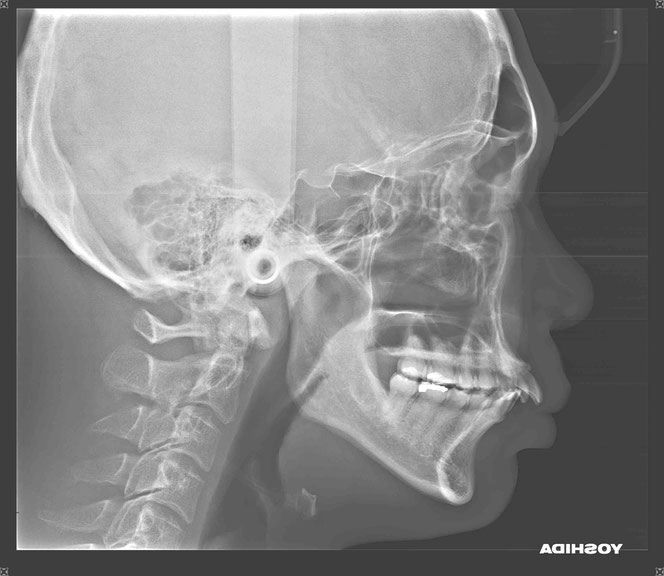

今回のケース

矯正治療後に奥歯の歯ぐきが2~3ミリ退縮。

その結果、露出した根の一部が虫歯になっていました。

「歯並びはきれいになったのに、今度は虫歯…」

そんな状態です。